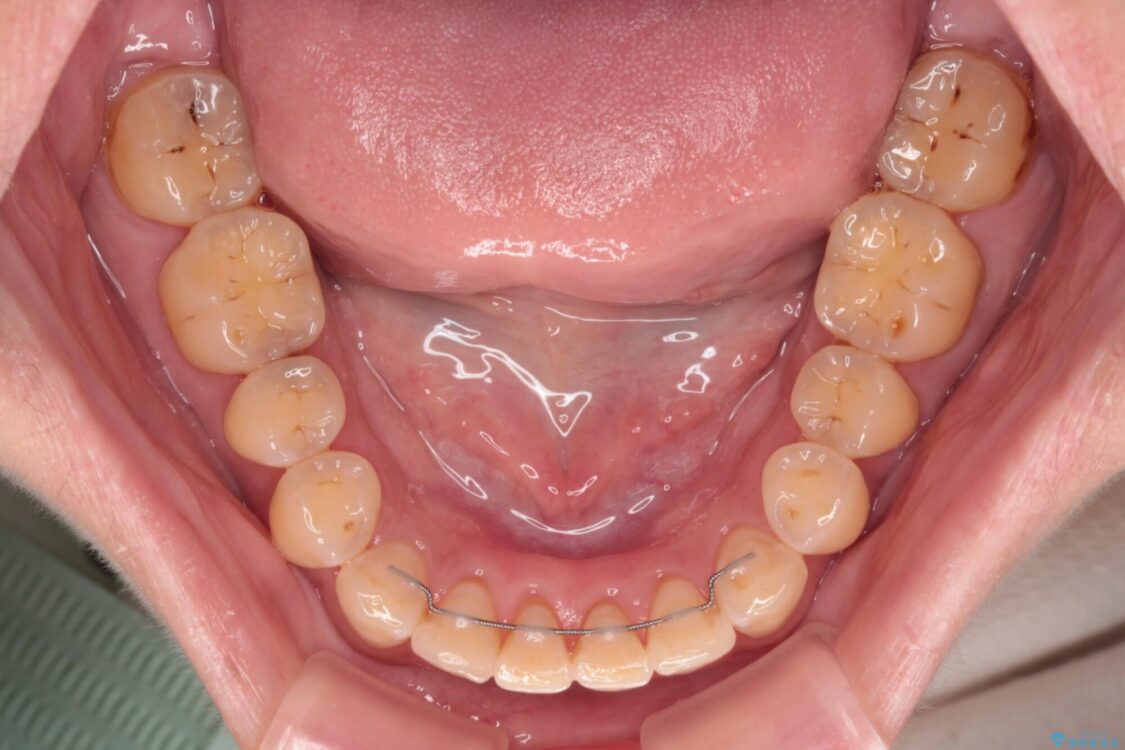

飛び出た上の前歯を気にして来院された患者様です。

奥歯の咬み合わせは、上顎歯列が理想的な一よりも数mm前方にある状態でした。

なるべく早めに治療を終えたいとのことで、補助装置を用いて上顎臼歯を後方に移動させ、同時にワイヤー装置にて整えることとしました。

治療途中

• 【モニター】飛び出た前歯を整えたい ワイヤー矯正治療 治療途中画像